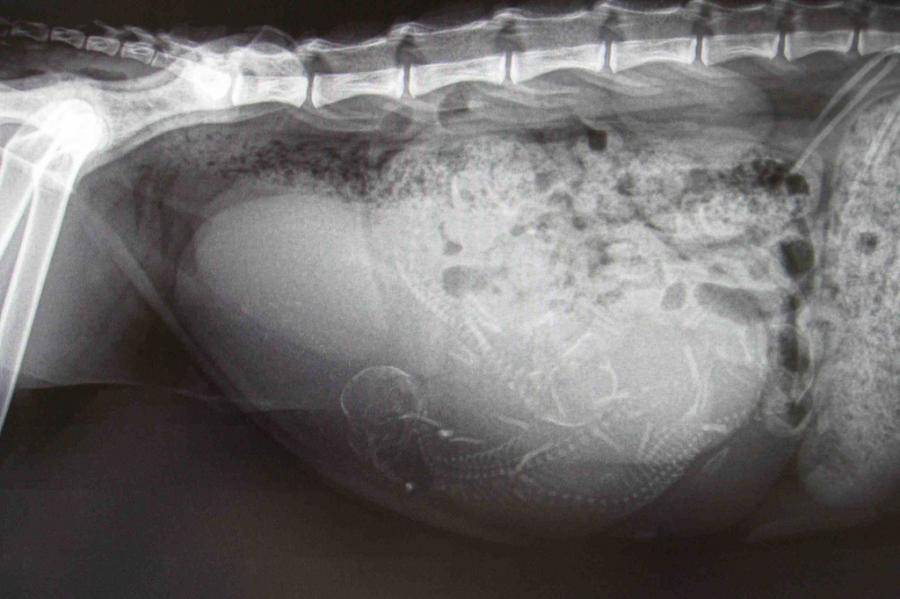

• Une radiographie est recommandée entre 50 et 55 jours car c’est le moment idéal pour compter les bébés et pour savoir s’ils passeront bien au niveau du bassin.